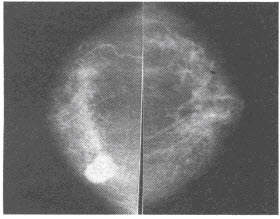

女,38岁,右侧乳腺内肿块,质韧不硬,易推动,拍片如图所示,应首先考虑()

A:乳腺小叶增生症

B:乳腺导管内乳头状瘤

C:乳腺癌

D:乳腺纤维腺瘤

E:乳腺脂肪坏死